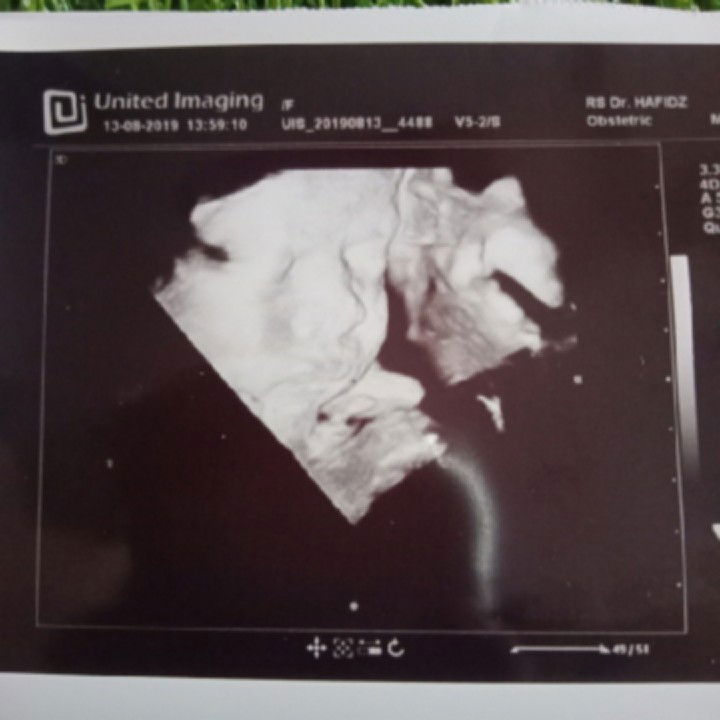

Bun ini baby ku kmrin pas USG, ada yg 36weeks?? Gmn prasaan nya deg2an ga hhi Trs hpl nya tgl brp?? Sama ga kya aku 17september